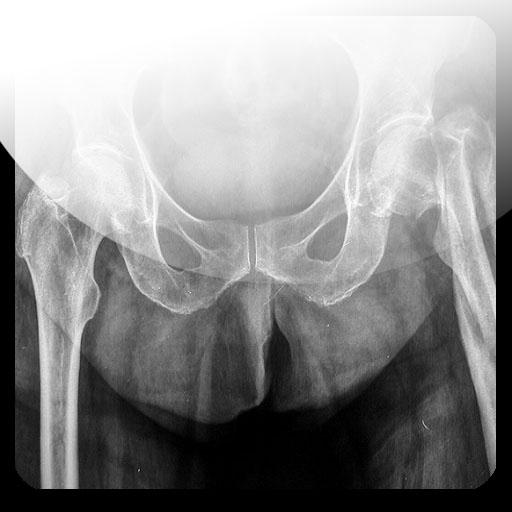

Hemos realizado una pequeña colección de las radiografías básicas presentes en los actuales exámenes de radiología en medicina, fisioterapia y enfermería.

Sabemos que faltan muchas pero hemos puesto las que más se han repetido en los exámenes que hemos revisado.